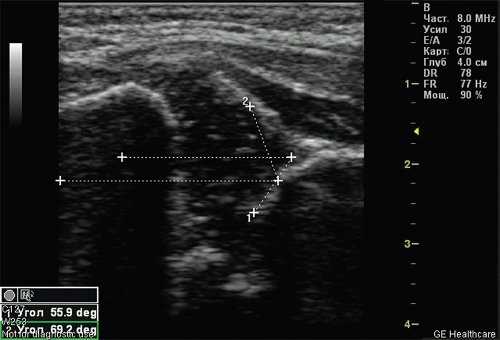

Тип 2б тазобедренных суставов выявлен у 25 (6,33%) детей - дисплазия тазобедренных суставов у детей старше 3 мес (рис. 4). Костная вертлужная впадина недостаточно развита, костный эркер закруглен, костнохрящевое соотношение меньше 2/3, хрящевая часть крыши охватывает головку бедренной кости. Угол α меньше 59°, но больше 50°, угол β больше 60°.

Рис. 4. Тазобедренный сустав тип 2б.

1 - угол α=53,4°;

2 - угол β=62,6°.